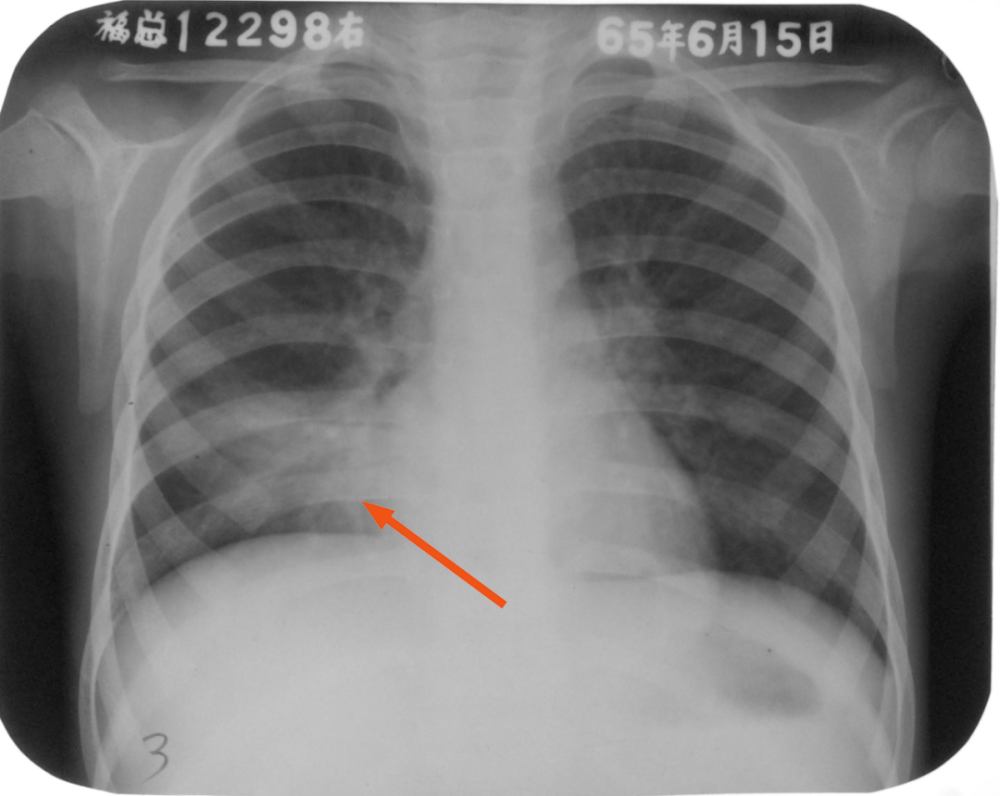

正常胸片 大叶性肺炎

症状不典型的大叶性肺炎

大叶性肺炎?但体征不明显,如图